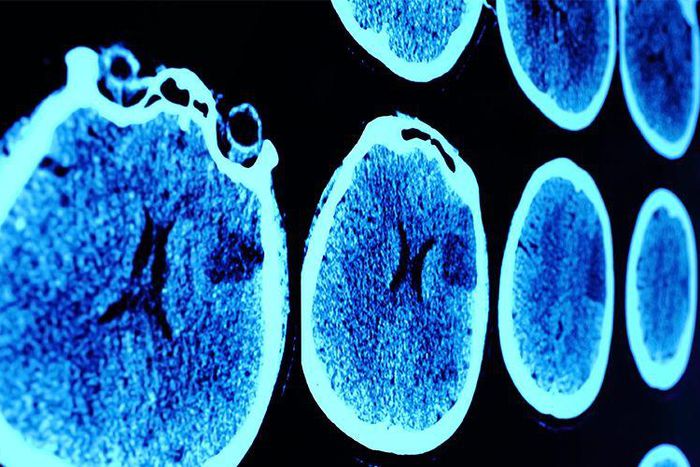

Brain cancer: Thats a really scary term. Luckily, theres a less than 1 percent change youll develop a malignant brain or spinal tumor in your life, according to the <a href="https://www.cancer.org/cancer/brain-spinal-cord-tumors-adults/about/key-statistics.html" id="f45bfc67-d3f5-36ec-ab00-a2ebdee8638c"> American Cancer Society </a> . Still, the <a href="https://www.cancer.org/cancer/brain-spinal-cord-tumors-adults/about/key-statistics.html" id="7c40b522-55c3-339e-a5f7-6f36a29d098b"> ACS </...

Brain cancer comes in two varieties: Primary tumors, which start in the brain and rarely spread, and secondary tumors, which start elsewhere in the body (typically the lungs or breasts) and spread to the brain, says Adilia Hormigo, M.D., Ph.D., director of neuro-oncology at the Mount Sinai Health System and associate professor of neurology, medicine and neurosurgery at the Icahn School of Medicine at Mount Sinai.

Over time, brain cancer can impact surrounding brain cells to seriously compromise brain function. And while that's true of all brain tumors, malignant or benign, cancerous tumors are more likely to spread throughout the brain, and quickly, according to Hormigo. That's why malignant tumors require aggressive treatments, typically including surgery, radiation, and/or chemotherapy , she says.